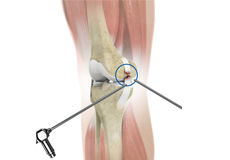

Arthroscopic Debridement

Arthroscopic debridement or a clean-up is a surgical procedure performed using an arthroscope. In this procedure, the cartilage or the bone that is damaged is removed using surgical instruments and the edges of the articular cartilage that are rough will be smoothened.

Knee Arthroscopy

Knee arthroscopy is a common surgical procedure performed using an arthroscope, a viewing instrument, to diagnose or treat a knee problem.